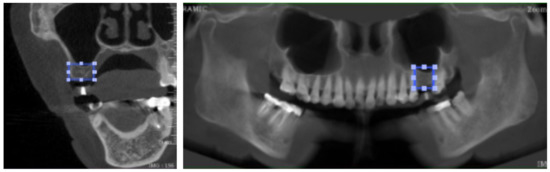

A total of 316 images were then anonymously captured to ensure that no private information was revealed. The full-screenshot images were taken from DTP software with the joint photographic expert group (JPEG) format at 1920 × 1080 pixels with 24-bit depth (Figure 1). Three hundred images were used for model training, which were randomly sorted from 1–300 to create six data sets, including 1–50, 1–100, 1–150, 1–200, 1–250, and 1–300. These six data sets were called the training set. The remaining 16 images were selected for accuracy testing to assess the performance of the developed model; this set of 16 images was called the testing set.

The labelled area in each image was generated in a square shape by connecting the four lines from the farthest border of the alveolar bone available for implant placement. The mentioned four lines included the upper border, lower border, mesial border, and distal border in a panoramic image, together with the upper border, lower border, buccal border, and lingual border in a cross-sectional image. The demonstration of the labelling process is displayed in Figure 2 and Figure 3a.

Figure 2. Image labelling in both cross-sectional and panoramic images.